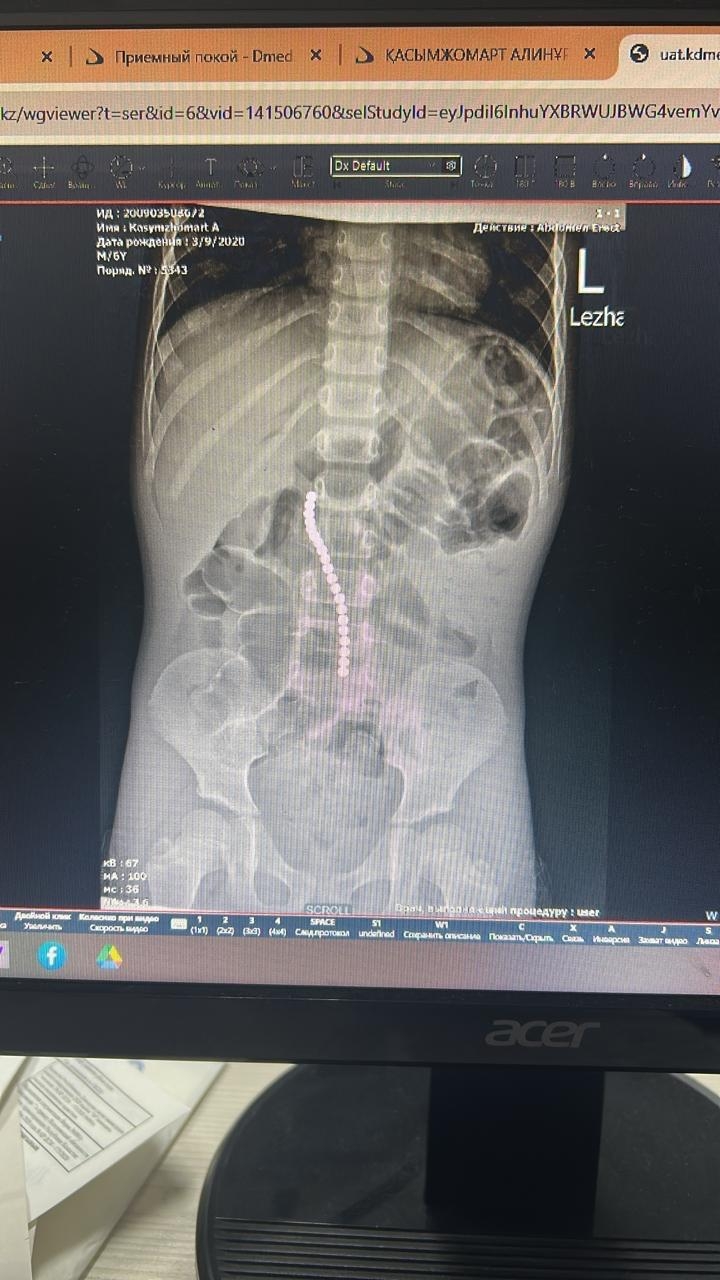

После оперативной диагностики врачи установили, что в желудочно-кишечном тракте ребёнка находилось сразу 20 магнитов. Инородные тела уже начали вызывать тяжёлые осложнения.